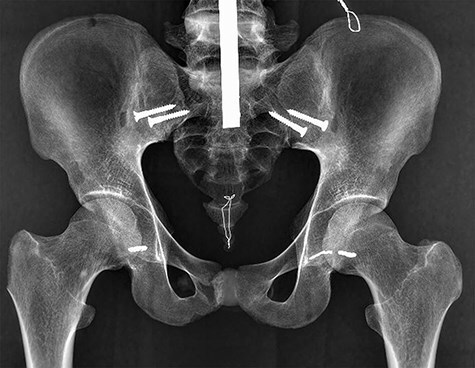

在评估股髋臼撞击的凸轮畸形时,头颈连接处(HNJ)必须准确评估。我们进行了这项研究,以确定平片显示HNJ端到端骨表面的能力。我们使用了6个人体骨骼模型。10名检查人员评估了重建计算机断层扫描中定义的1:00、1:30和2:00径向平面上附着的不锈钢丝标记物在x线平片上准确检测骨表面的程度。我们使用了13张x线平片:交叉桌侧位视图、蛙腿侧位视图、espieve蛙腿侧位视图、假侧位视图、修改假侧位视图、30°Dunn视图(DV)、45°DV、60°DV、90°DV、30°修改Dunn视图(MDV)、45°MDV、60°MDV和90°MDV。检查人员对放射图像准确检测HNJ骨表面不锈钢丝标记的程度进行评分,评分范围为1分(0%匹配)至5分(几乎100%匹配)。1:00飞机在45°DV上的最高得分为4.98分。同样,在1点30分和2点的最高分中,45°MDV为4.98分,90°MDV为4.68分。在这些骨模型研究中,在1:00、1:30和2:00平面上描述HNJ最合适的x线平片分别是45°DV、45°MDV和90°MDV。

In evaluations of a cam deformity on femoroacetabular impingement, the head-neck junction (HNJ) must be accurately assessed. We conducted this study to determine the ability of plain radiography to visualize the end-to-end bone surface of the HNJ. We used six human bone models. Ten examiners evaluated the degree to which attached stainless wire marker at the 1:00, 1:30, and 2:00 radial plane defined in reconstructed computed tomography can be accurately detected on the bone surface on plain radiographies. We employed 13 plain radiographies: the cross-table lateral view, frog-leg lateral view, Espié frog-leg lateral view, false-profile view, modified false-profile view, 30° Dunn view (DV), 45° DV, 60° DV, 90° DV, 30° modified Dunn view (MDV), 45° MDV, 60° MDV, and 90° MDV. Examiners scored the degree to which the radiographic images accurately detected the stainless wire marker on the bone surface of the HNJ on a scale of 1 point (0% match) to 5 points (almost 100% match). The highest score for the 1:00 plane was 4.98 points on the 45° DV. Similarly, the highest scores of the 1:30 and 2:00 planes were 4.98 points for the 45° MDV and 4.68 points for the 90° MDV, respectively. On these bone model studies, the most suitable plain radiography for describing the HNJ at the 1:00, 1:30, and 2:00 planes were both the 45° DV, the 45° MDV, and the 90° MDV, respectively.